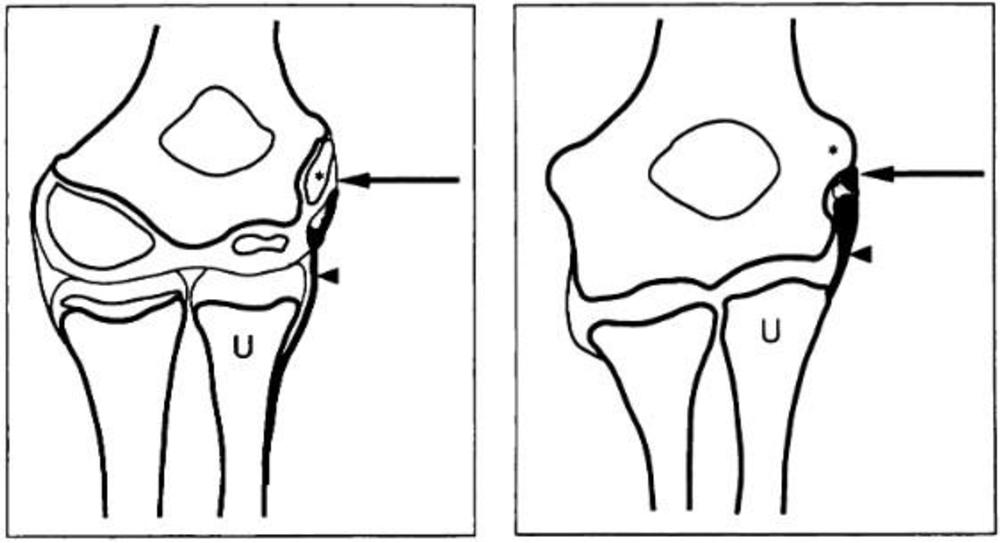

Figure 1. Elbow images. In image on the left (10-year-old boy), growth plate has not yet fused. On the right (15-year-old boy), growth plate has fused. (Courtesy of Radiology)

Figure 3. Sketch of developing elbow, before and after growth plate closure. (Courtesy of Radiology)